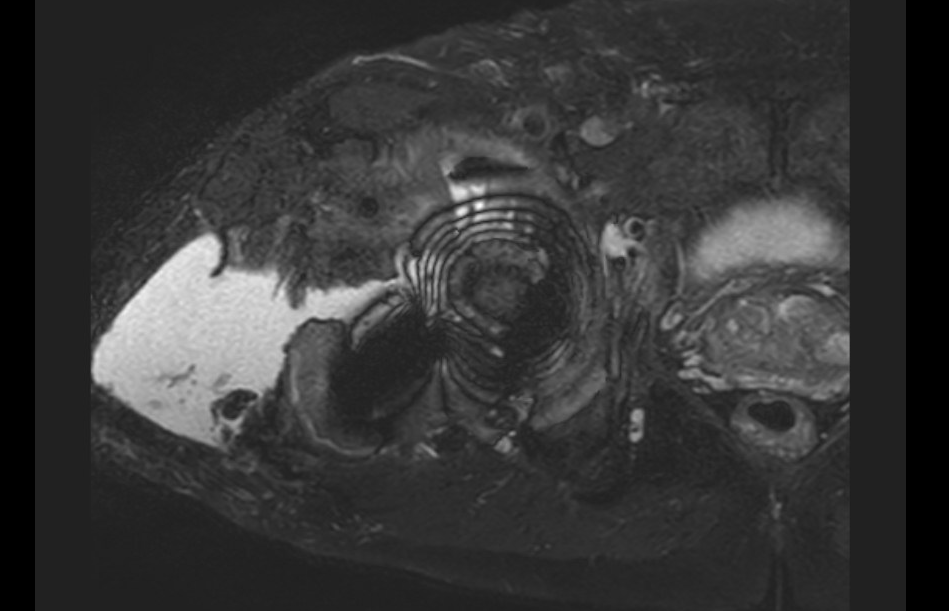

MRI / CT

MRI demonstrating large fluid collection around THA